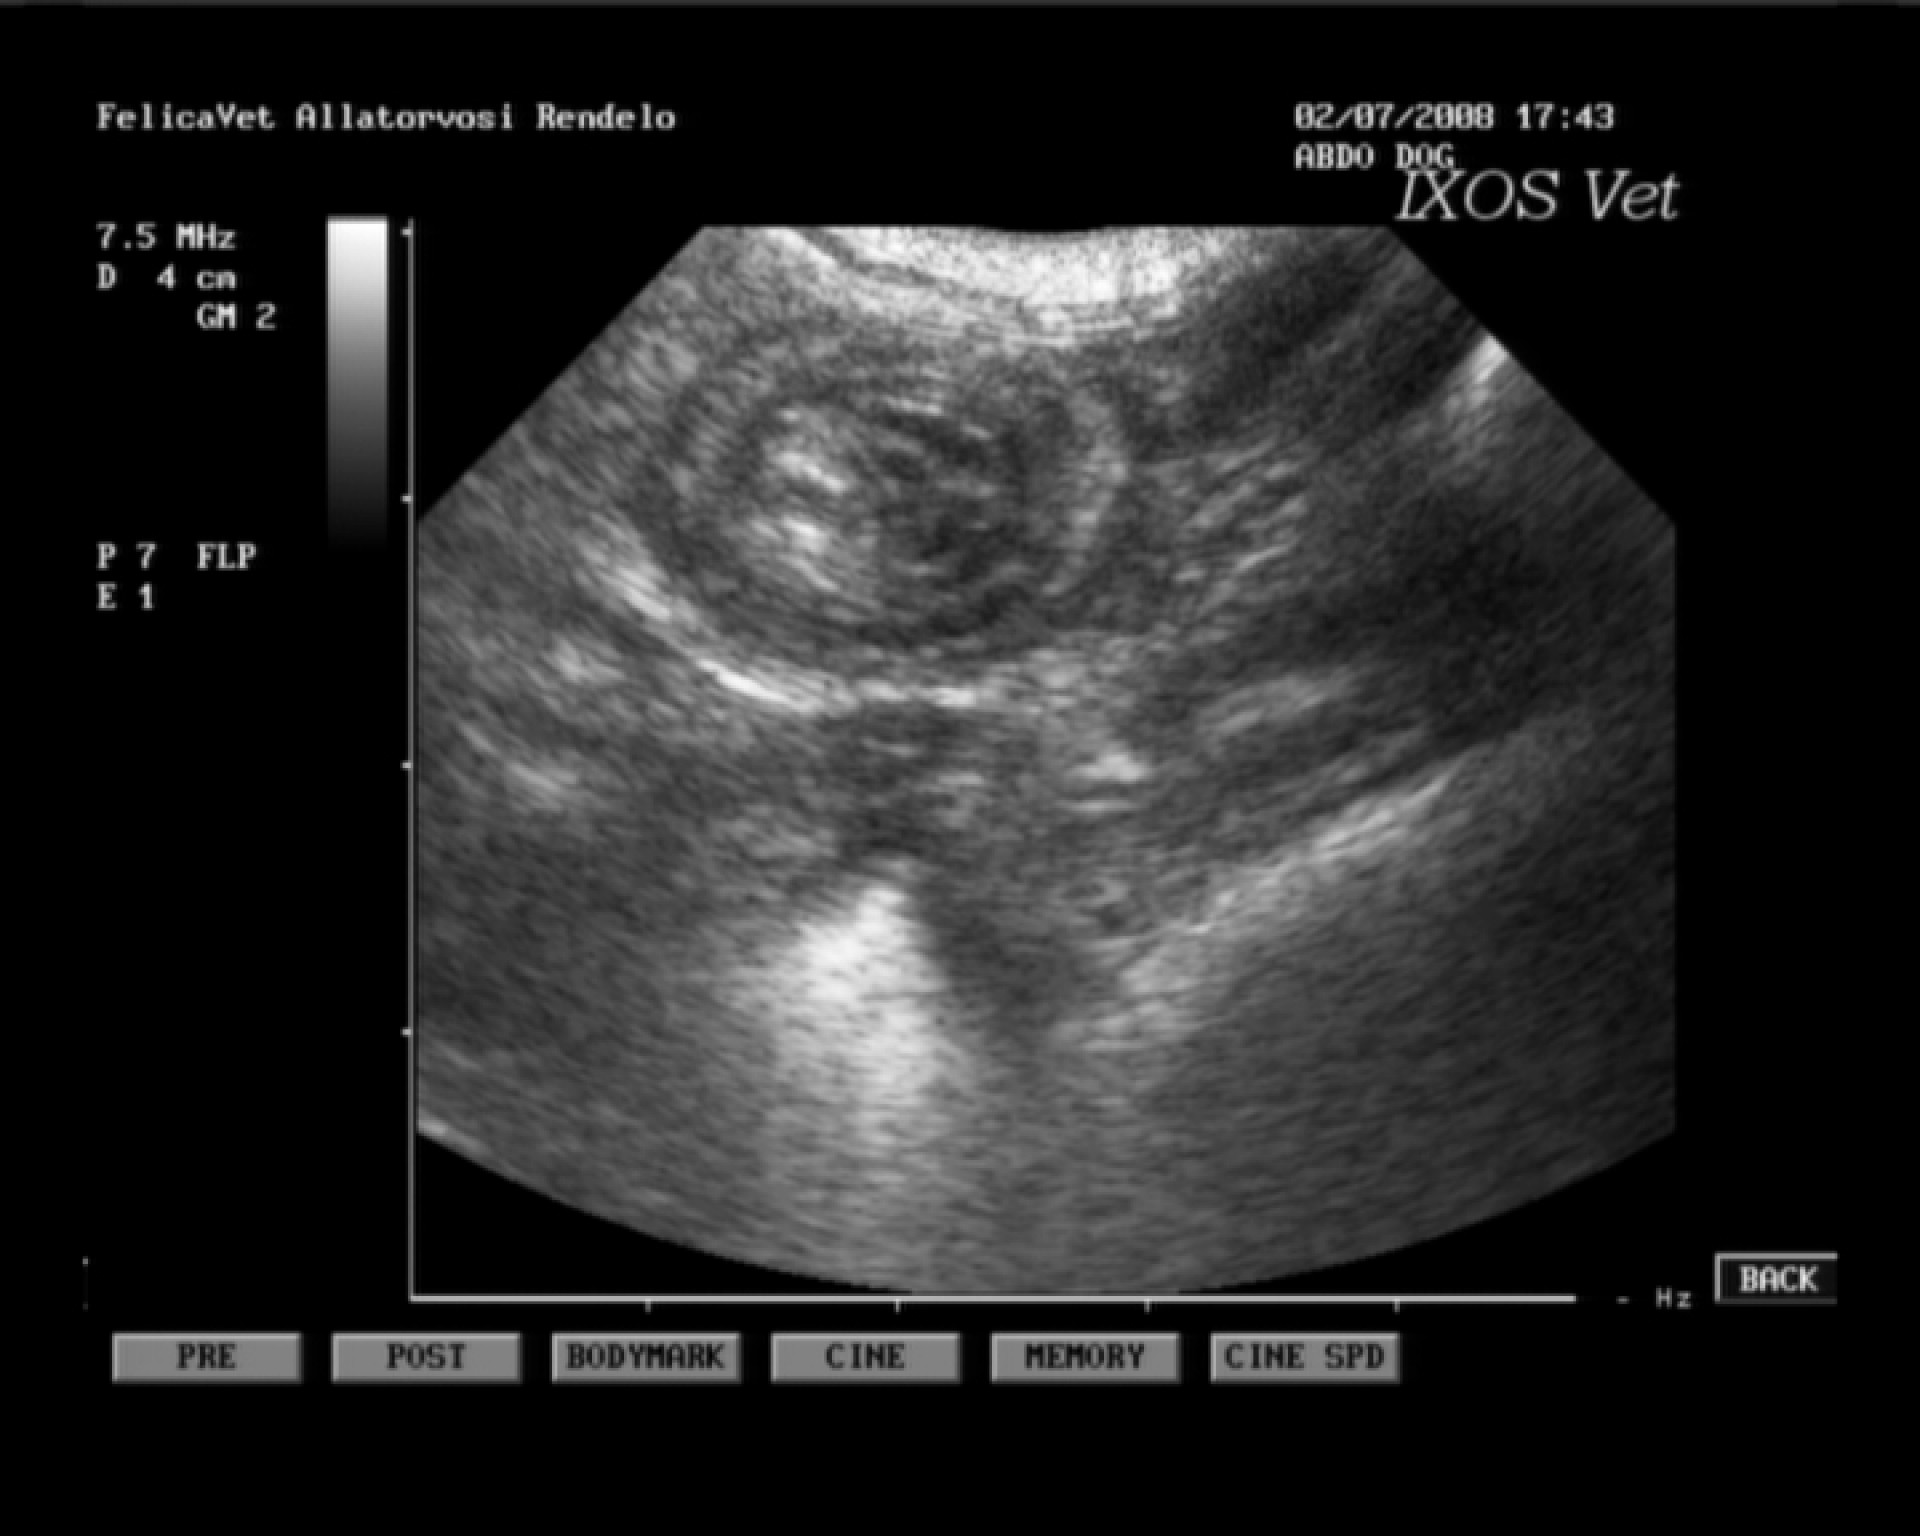

A különféle bélelzáródások diagnosztikája során a kórelőzmény (pl.: játék lenyelése) és a klinikai tünetek (hányás, a has feszítése, tapintható idegentest a hasüregben stb.) mellett kiegészítő vizsgálatként RTG vizsgálat és a hasüreg ultrahangos vizsgálata jöhet szóba. A bél elzáródását okozó képletek az esetek döntő többségében nem adnak röntgen árnyékot, ezért un.: röntgen kontrasztanyagot etetünk az állattal és többszöri röntgenfelvétel készítésével figyeljük a tovahaladását.

Abban az esetben, ha a kontraszt anyag elakad, az ileus diagnózisa nagy biztonsággal kimondható. Ultrahangos vizsgálattal a bélelzáródás előtti területen felhalmozódó béltartalom un.: inga-mozgása is egyértelműen bélelzáródásra utaló diagnosztikai jel.